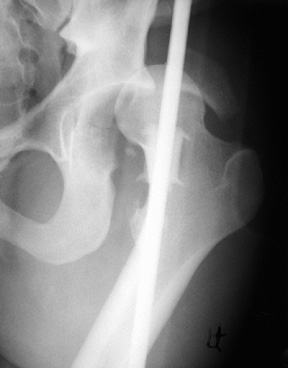

骨折與創傷8 / 9

【112-1 醫學(五) 第73題】20歲男性病人因車禍左髖關節腫痛。圖為本次就診之左髖關節X光攝影及電腦斷層影像。最可能的診斷為何?